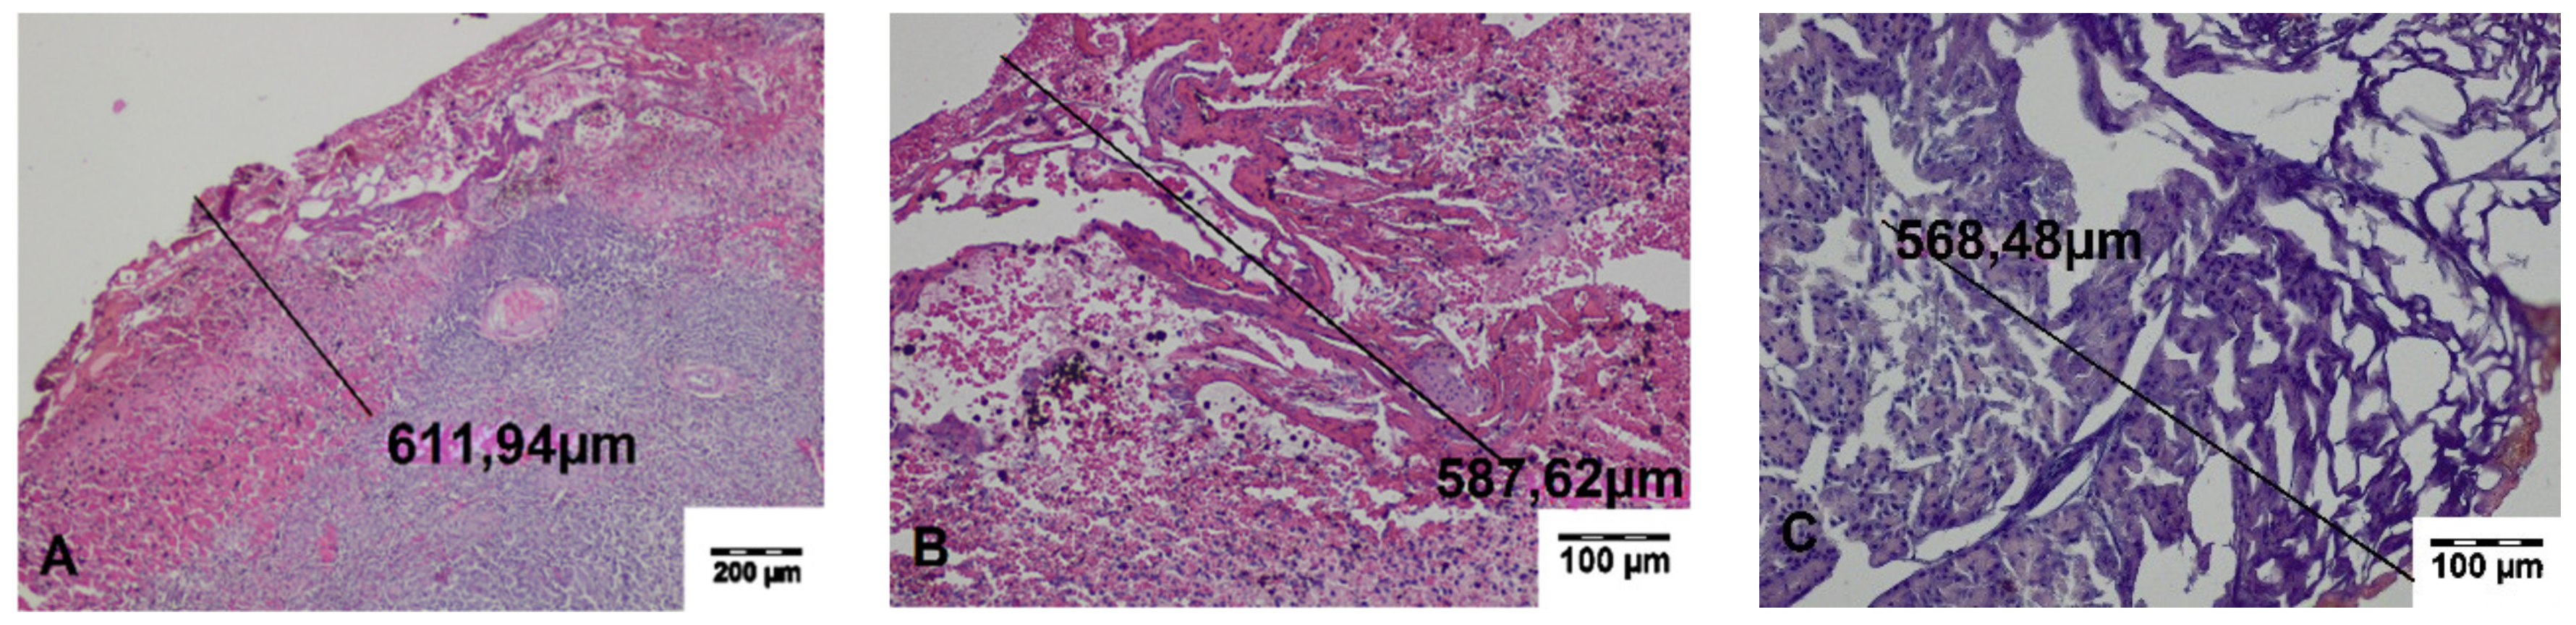

In the specimens collected during the surgery, a zone of carbonized tissue with exudation free of erythrocytes or with a small number of extravasated erythrocytes, as well as a zone of altered tissue, was visible. In the immediate vicinity of the incisions, superficial carbonized amorphous necrotic structures with an average width of 197.29 ± 35.99 μm for TDFL and 313.44 ± 20.89 μm for DL were found. The deeper zone was characterized by slightly shrunken cells with preserved cell nuclei, sharply demarcated from the surrounding normal tissue. The average width of both zones of thermal tissue damage was 655.26 ± 107.70 μm for TDFL and 1413.37 ± 111.85 μm for DL (Figure 3 and Figure 4, Table 2).

Figure 3. Histopathological sections of the spleen fragments collected intraoperatively, showing changes produced by the thulium-doped fiber laser (TDFL). Black lines indicate the width of the entire zone of thermal damage (hematoxylin and eosin (HE) staining). (A) A superficial zone of carbonization and a deeper zone of thermal changes are present in the spleen parenchyma (magnification × 40); (B,C) magnification × 100.